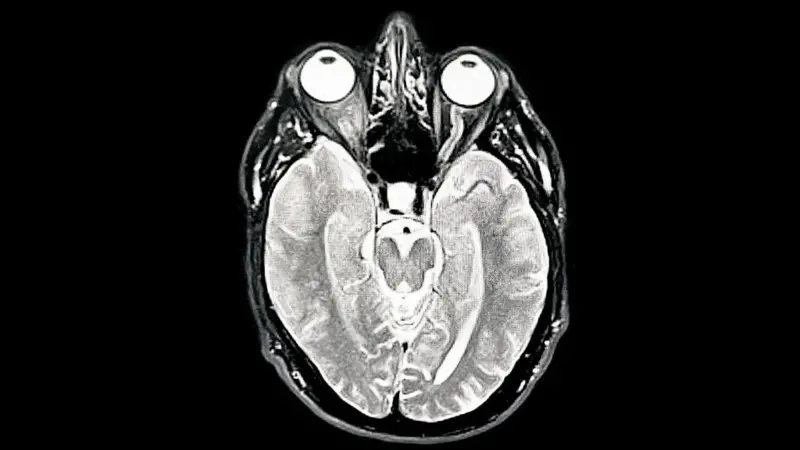

La investigación, publicada en Nature Communications, analizó cerca de 4,000 escáneres cerebrales de personas entre 0 y 90 años.

Los científicos demostraron que el cerebro no evoluciona de manera lineal, sino que atraviesa fases de reconfiguración profundas.

A los 9 años inicia la adolescencia cerebral, un periodo que dura hasta los 32 y se caracteriza por un aumento notable en la eficiencia de las conexiones.